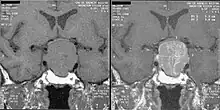

An MRI of the brain focusing on the sella turcica after gadolinium administration allows for clear delineation of the pituitary and the hypothalamus and the location of the tumor. A number of other overgrowth syndromes can result in similar problems.